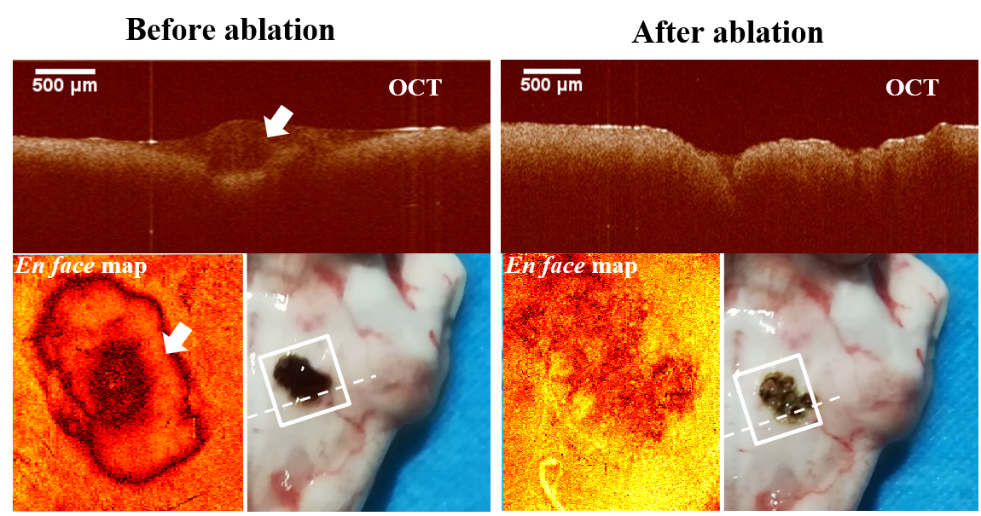

OCT引导激光消融前后肿瘤区域(白色箭头指向肿瘤)